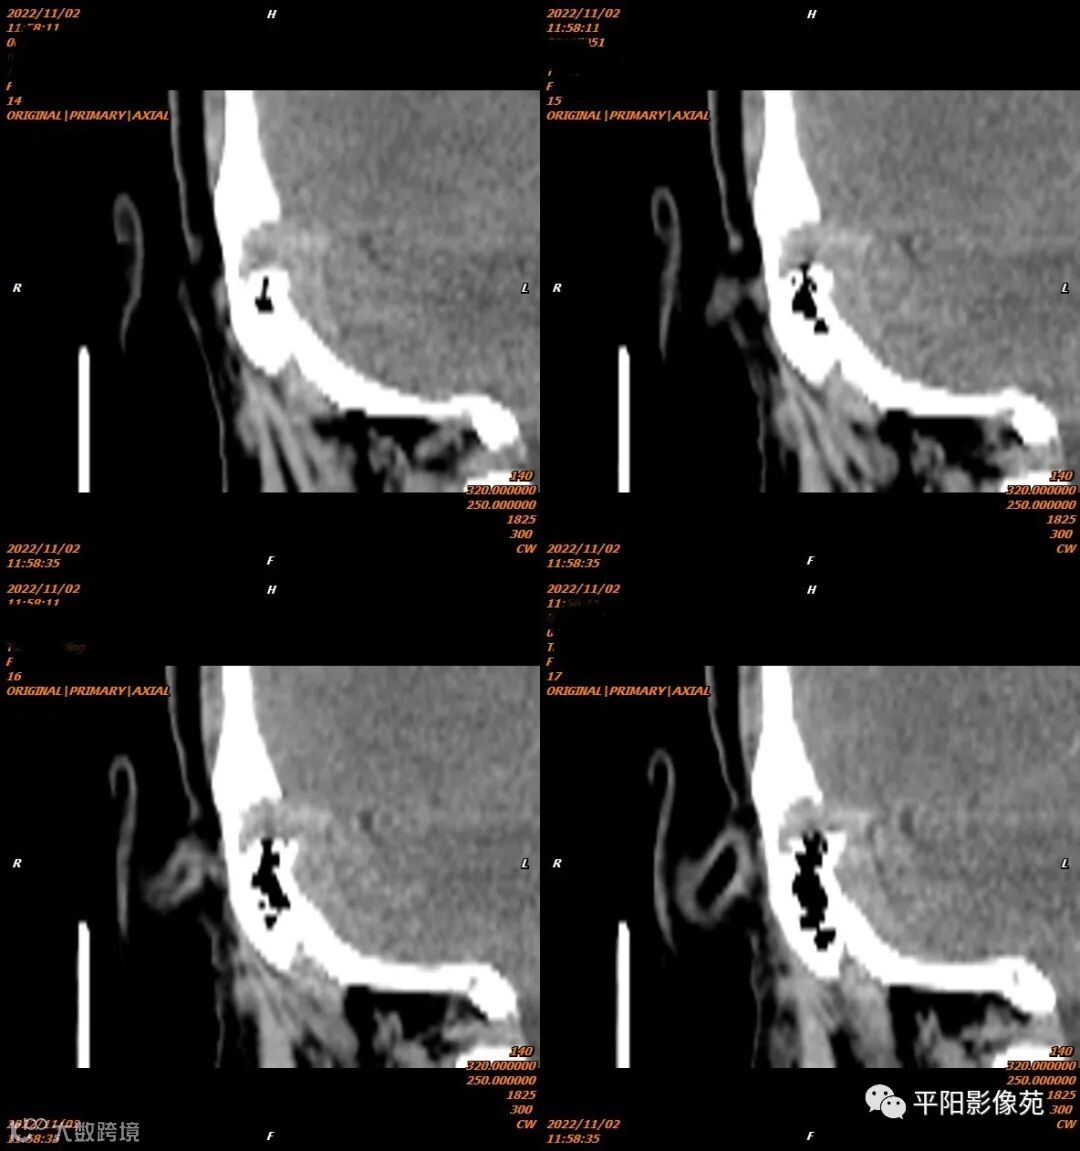

影像表现

影像表现:乙状窦局限性扩大,向右侧膨出,压迫右侧颞骨凹陷,前方乳突气房骨壁缺损。

影像诊断:乙状窦憩室